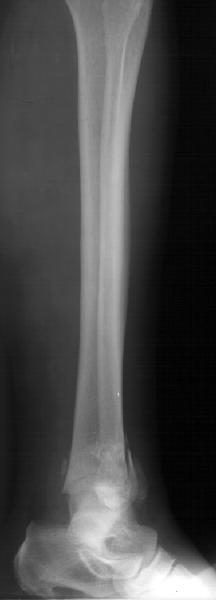

Subject: Tibia Fx - Comminuted Supramalleolar - Open

Middle aged adult was injured while travelling in a train(accidentally put his leg out). Presented with injury to left lower leg. Lacerated wound over the fibular fracture. Also another wound over the foot anterolaterally. No deficits.

On day one wound debridement followed by calcaneal traction done. Needs further stabilisation and a small split graft laterally. At present the fragments are putting pressure on the anterior skin. Will be happy to get your opinion on possible methods of stabilisation.

Day 1

Traction